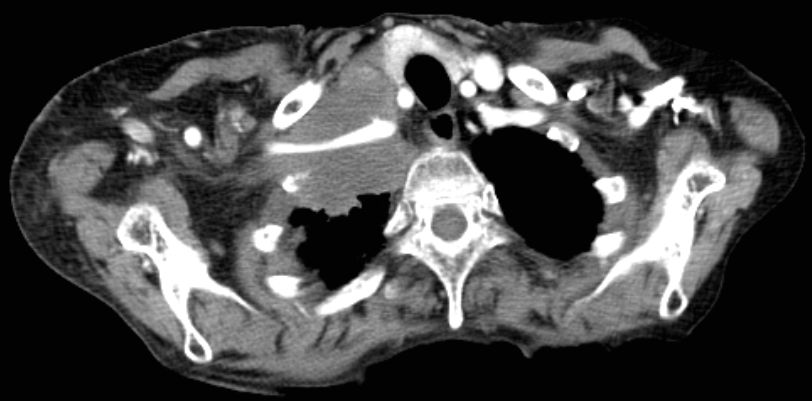

| Pancoast linker Oberlappen | 63-jähriger Mann mit einem Plattenepithelkarzinom

des linken Lungenoberlappens. Klinisch faustgroßes Vorwölbung über dem

linken Schlüsselbein.![]() |

Die Infiltrate haben die A. subclavia

eingeschlossen. Klinisch schlaffe Lähmung des linken Arm mit lividität.

Zusätzlich Verengung des Lidspaltes links.![]() | |